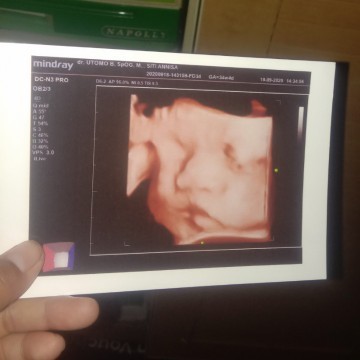

30 minggu bun

38week

USG 28w....